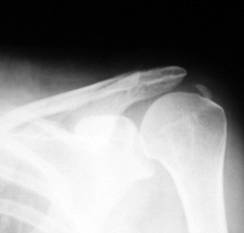

Periartrita scapulohumerala in faza acuta nu are corespondent radiologic. In faza cronica se constata depuneri calcare in tesuturile periarticulare si modificari osoase trohiteriene: spiculi ososi si osteoscleroza radiara a corticalei.

Fig. 355 Periartrita scapulo-humerala

Articulatia scapulohumerala nu este modificata.